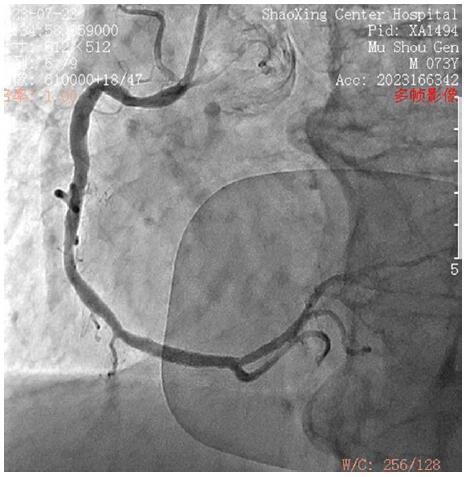

Immediate management included discontinuing ceftriaxone, emergency tracheal intubation, and intravenous epinephrine. Emergency coronary angiography showed no significant coronary artery stenosis. Postoperatively, the patient received antiplatelet therapy, plaque stabilization, and vasodilation in the intensive care unit.

立即处理包括停用头孢曲松、紧急气管插管和静脉注射肾上腺素。急诊冠状动脉造影显示无明显冠状动脉狭窄。术后,患者在重症监护病房接受抗血小板治疗、斑块稳定和血管舒张治疗。